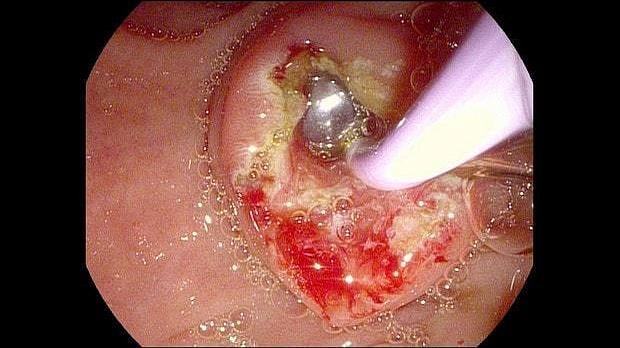

Здравствуйте. Пациентка, 32 года. Поступила на хирургическое отделение с диагнозом ЖКБ: холедохолитиаз. По данным МРТ: ЖКБ, множественные мелкие конкременты холедоха. При дуоденоскопии выявлено наличие вклиненного конкремента большого дуоденального сосочка. Выполнена прекатсфинктеротомия, получено 3 конкремента, диаметром около 0.4-0.5 см. Далее канюляция холедоха проволочным папиллотомом, выявлены многочисленные конкременты холедоха. Выполнена литоэкстракция ревизионным баллоном (на последнем фото окклюзионная холангиография - в просвете холедоха не конкременты, а пузырьки воздуха)).